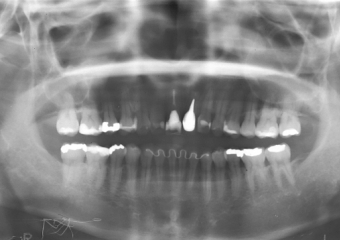

Raio X com dente de porcelana instalado

Imagem final do caso terminado em janeiro de 2013